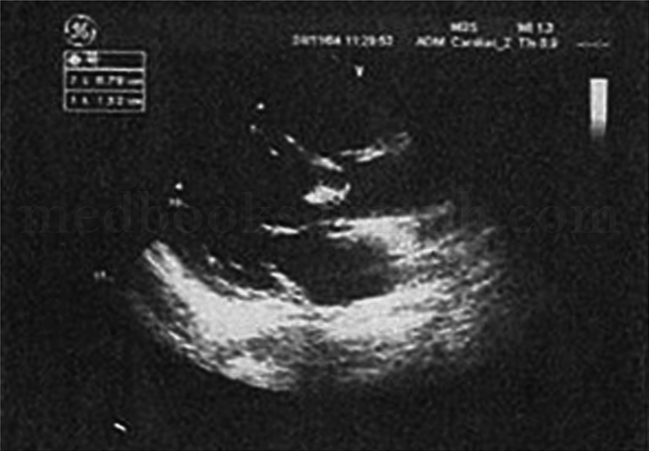

1小时条评论者,男性,53岁,主因间断发热伴体重下降2个月于2004年8月15日首次来笔者医院急诊就诊。 患者自2004年6月无明显诱因出现午后发热,体温波动于38.5~39℃,最高为39℃,伴畏寒和食欲下降,晨起体温正常。无咳嗽、咳痰,无腹痛、腹泻以及尿频、尿急等症状,无盗汗、皮...